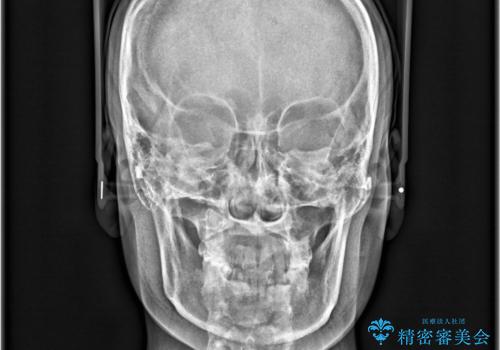

- 「下の前歯が斜めになっている」を主訴に来院された患者様です。

下顎前歯に叢生があり、右上2は反対咬合の状態でした。

下顎前歯の叢生がとれ右上2の反対咬合も改善し患者様にも満足していただけました。治療期間は1年~1年半を見込んでいましたが、患者様の協力もあり10か月で矯正を終えることが出来ました。